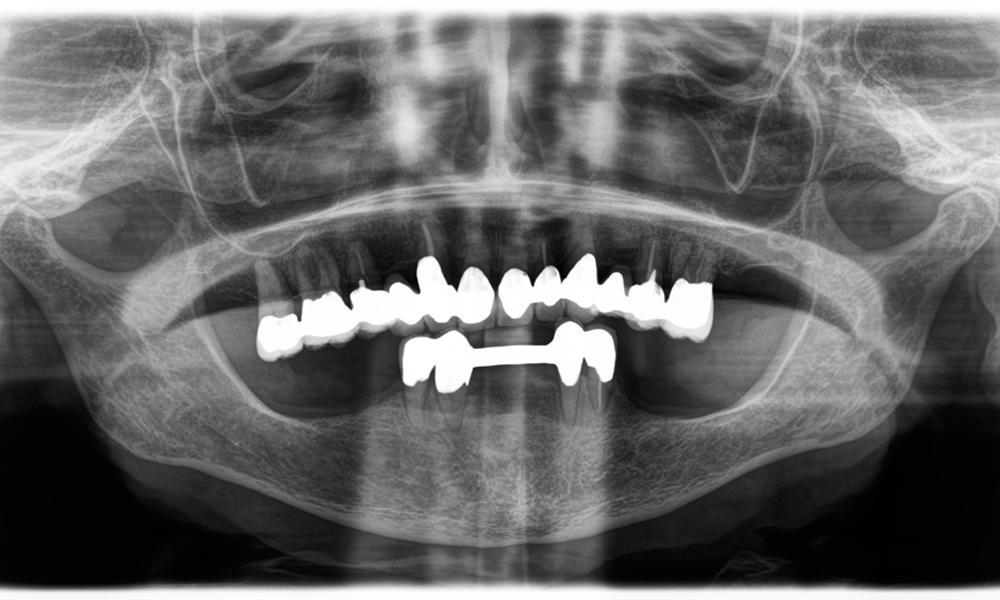

Dr. Wolfgang Tautschnig, ein erfahrener Zahnarzt aus Salzburg, hat die Synea Power Edition über mehrere Monate hinweg in seiner Praxis in verschiedenen klinischen Szenarien eingesetzt und evaluiert. Darunter vor allem für das Entfernen von Zirkonkronen und das Bearbeiten von unedlen Legierungen. In einem konkreten Fall stellte sich eine 81-jährige Patientin mit dem Wunsch nach einer ästhetischen Verbesserung ihrer 40 Jahre alten VMK-Kronen vor. Die bestehenden Kronen entsprachen nicht mehr den ästhetischen Ansprüchen der Patientin. Die Herausforderung lag in der Entfernung von zwölf verblockten Kronen mit unedler Legierung, ohne die darunterliegenden Zahnstümpfe zu beschädigen. Das Winkelstück wurde genutzt, um die Keramikschichten präzise einzuschlitzen sowie die Metallgerüste mit einem Hartmetallfräser zu trennen, um so die Kronen mit minimalem Trauma zu entfernen. Innerhalb von nur 30 Minuten waren die alten Kronen entfernt, danach konnte die neue Arbeit, bestehend aus Vollzirkon im Seitenzahnbereich und verblendeten Kronen im Frontzahnbereich, vorbereitet werden. Das Ergebnis war eine vollständige Neuanfertigung, die sowohl funktional als auch ästhetisch überzeugte (siehe Abb. 1).

Ein weiteres Beispiel für die klinische Leistungsfähigkeit der Power Edition war der Austausch einer beschädigten Zirkonkrone bei einer 63-jährigen Patientin. Diese stellte sich aufgrund eines abgesplitterten Verblendungsteils ihrer 20 Jahre alten Zirkonkrone an Zahn 6 vor. Trotz der Position im Seitenzahnbereich empfand die Patientin dies als störend und wünschte eine neue Krone.

Die Power Edition ermöglichte eine präzise Schnittführung, wobei das erhöhte Drehmoment und die verbesserte Kühlung dazu beigetragen haben, die Krone ohne größeren Materialverlust zu entfernen. Das Spannsystem und das verbesserte Drehmoment erwiesen sich hierbei als essenziell.